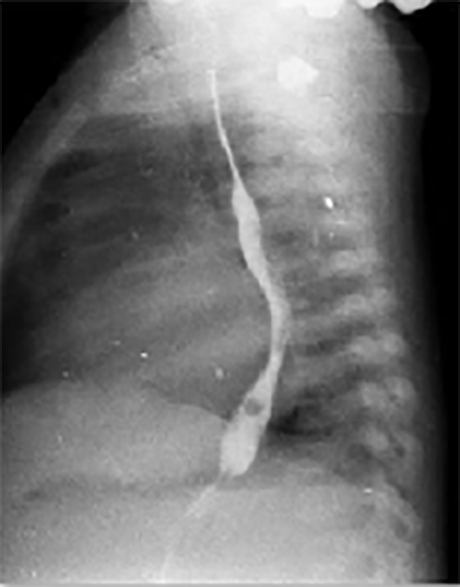

PA and Lateral

Click on the xrays to enlarge them.

Choose the best interpretation of the chest X rays:

RV enlargement, dilated

pulmonary trunk, increased pulmonary

arterial vascularity

LA/biventricular enlargement,increased pulmonary arterialvascularity

LV enlargement, aortic dilatation

RV hypertrophy, smallpulmonary trunk, decreasedpulmonary arterialvascularity

Dilated pulmonary trunk, normal vascularity